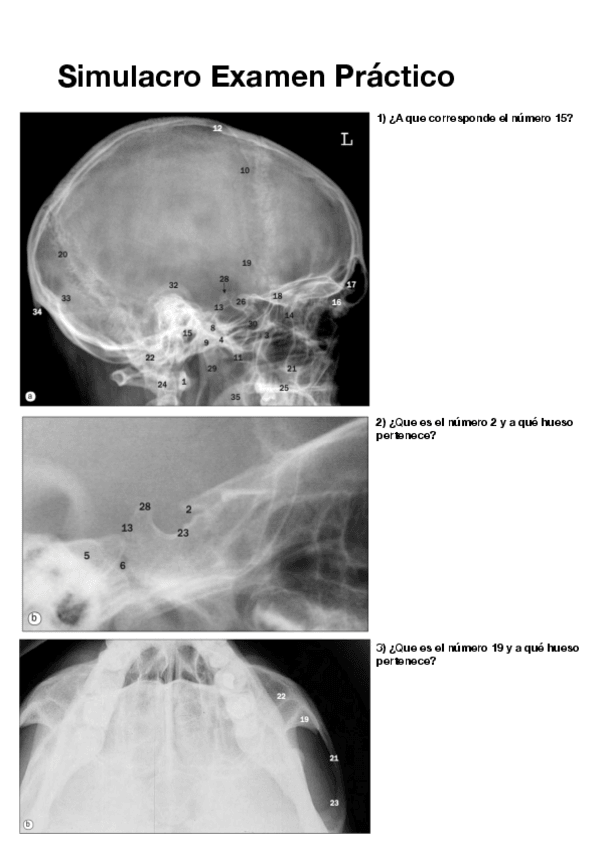

Simulacro-Examen-Practico-pdf.pdf

Apuntes - Simulacro-Examen-Practico-pdf.pdf